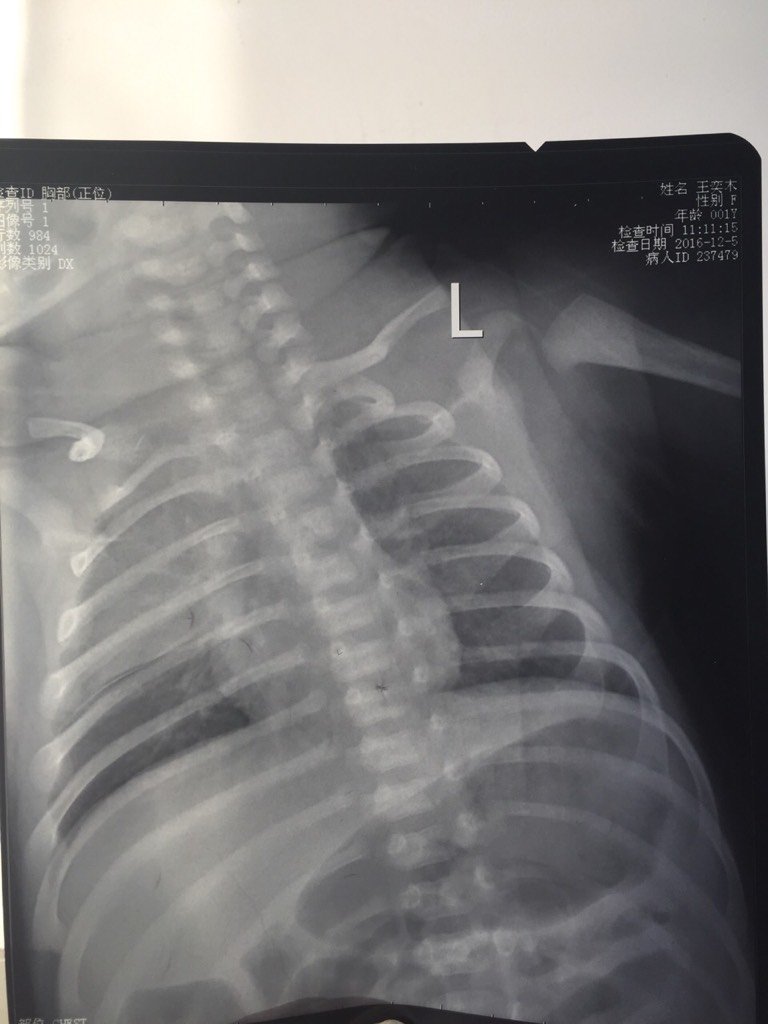

专家您好,我家宝宝36天的时候,嘴里吐泡泡,偶尔咳嗽,精神好吃奶正常!去医院检查,医生听诊器没听听还可以,说是有点支气管炎,开了正大素克克洛己新干混悬剂和小儿消积止咳口服药回来吃,吃了三天去复查,听诊器听着呼呼的,后来拍了肺部片子,下面片子说是大叶性肺炎了!然后住院治疗一周后,治愈出院!现在偶尔还是会咳嗽,然后吐泡泡,吃完奶,总觉得喉咙有呼呼的声音,口水有点黏糊糊的,吃奶正常,精神也可以,就是白天睡觉基本靠抱着睡,喜欢竖着抱在怀里面,一放床上就醒!请问这是又复发了吗?